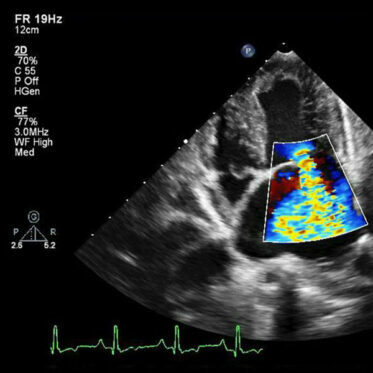

Echokardiografia: to podstawowa, obrazowa metoda badania serca i naczyń krwionośnych za pomocą ultradźwięków. Na ekranie uzyskujemy obraz, powstający w wyniku odbicia fal ultradźwiękowych od badanych struktur wewnątrz ciała. W sposób nieinwazyjny i bezpieczny dla Pacjenta umożliwia obrazowanie struktur anatomicznych serca, ruchu zastawek, ocenę kurczliwości mięśnia sercowego oraz przepływu krwi. W badaniu możliwe jest zobrazowanie także dużych naczyń krwionośnych, do których zaliczamy aortę, tętnice płucne oraz żyły główne.

Do najważniejszych wskazań do wykonania badania zaliczamy:

– ocena kurczliwości mięśnia sercowego: po zawale serca, zabiegach interwencyjnych w stabilnej chorobie wieńcowej (angioplastyka, pomostowania aortalno-wieńcowe (tzw. „bypassy”), zapaleniu mięśnia serca,

– ocena funkcji zastawek serca: zwężenia lub niedomykalności,

– ocena wad wrodzonych serca,

– ocena poszerzenia i dysfunkcji dużych naczyń: (np. tętniak aorty wstępującej, poszerzenie żył głównych, tętnicy płucnej),

– badanie kontrolne u wszystkich pacjentów z niewydolnością serca: regularna kontrola jest konieczna, aby przeciwdziałać stanom zaostrzenia niewydolności i zmniejszenie ryzyka częstszych hospitalizacji,

– ocena u pacjentów z kardiomyopatią serca i innymi wadami nabytymi,

– ocena przed zabiegami kardiologicznymi i niekardiologicznymi (np. przed operacją),

– ocena prawidłowej funkcji serca u osób uprawiających sport, w tym zawodowych sportowców,

– ocena podczas leczenia onkologicznego (przed operacją, przed, w trakcie i po chemio- i radio-terapii),

– badanie potrzebne jest również w diagnostyce u kobiet w ciąży.